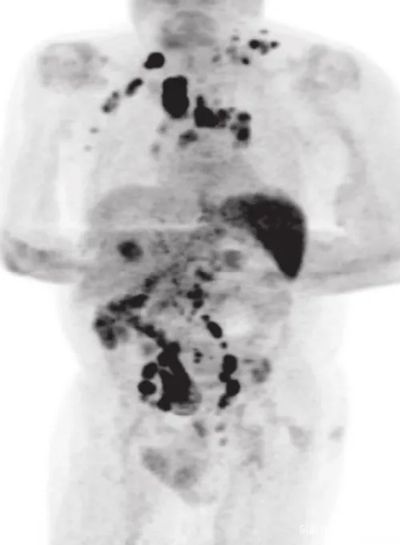

2020年年中,男子的身体突然之间暴瘦,并且全身淋巴结肿大,他赶紧到医院检查,结果确诊罹患经典型霍奇淋巴瘤,PET-CT扫描提示疾病分期为3期。

也就是说,男子此时是一名癌症晚期患者。CT照片也显示,癌细胞扩散到了他身体的各个地方。

图中所示黑色部分为癌细胞,下同

四个月后,男子回医院复查。PET-CT扫描却提示,他体内的大部分肿瘤竟然神奇地都消失了。更为夸张的是,与肿瘤有关的生物指标直接下降了约9成。